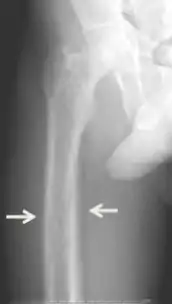

Los síntomas inespecíficos incluyen sensación de cansancio y sed, existen cambios de humor que incluyen, tristeza, debilidad y irritación junto con otros síntomas como el picor, dolor de cabeza, dolor articular, olvido y dolor abdominal.[8] [4] [9] [1] Los síntomas más específicos relacionados con los niveles de calcio y fosfato elevados en sangre incluyen dolor de huesos (osteodinia) y sensibilidad ósea que son comunes y están relacionados con sensibilidad de músculo proximal. Otros signos pueden incluir pancreatitis, piedras de riñón, calcificaciones corneales, adelgazamiento de huesos largos y calcificaciones hipodérmicas que pueden ser palpables en algunos pacientes.[2]

Las afecciones debidas a pérdida de hueso como la osteopenia y la osteoporosis son comunes en el hiperparatiroidismo terciario junto con las fracturas patológicas. Las pseudoacropaquias de los dedos también puede ser indicativo de un hiperparatiroidismo terciario severo debido a una resorción ósea excesiva en las falanges distales.[8] [1]

El diagnóstico incluye análisis tanto clínicas como de laboratorio. Las investigaciones radiológicas buscan signos de pérdida de hueso en manos y pelvis, rasgo característico hiperparatiroidismo terciario.[8] Otro examen clínico puede incluir la clasificación de la debilidad muscular, que se realiza pidiendo al paciente que se ponga de pie desde una posición sentada con las manos cruzadas sobre el pecho.[4] Los análisis de laboratorio incluyen determinación del nivel de calcio de sangre y de fosfatasa alcalina, los cuales están siempre aumentados en el hiperparatiroidismo terciario. Otros resultados comunes de laboratorio incluirían niveles disminuidos de vitamina D, hormona paratiroidea elevada de sangre elevada e hiperfosfatemia.[9] [1]